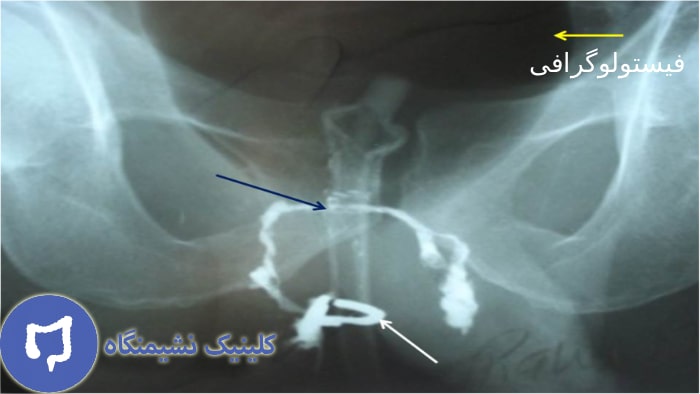

فیستولوگرافی

همان طور که از اسمش پیداست، فیستولوگرافی روش تشخیصی مختص به فیستول بوده که قادر است تا مسیر و شاخه های فیستول مقعدی را نمایان کند.

در این روش، پزشک ماده حاجب را از طریق دهانه خارجی فیستول به داخل مسیر آن تزریق کرده و سپس با استفاده از اشعه ایکس یا فلوروسکوپی از ناحیه تصویربرداری میشود. این تصاویر به وضوح مسیر اصلی فیستول، طول آن و در برخی موارد ارتباط احتمالی با مجرای مقعد را نشان می دهد. هرچند امروزه دقت روشهایی مانند ام ار ای لگن یا سونوگرافی فیستول بیشتر است، اما فیستولوگرافی همچنان در برخی مراکز برای تشخیص اولیه و بررسی شکل آناتومیک فیستول های ساده مورد استفاده قرار می گیرد.